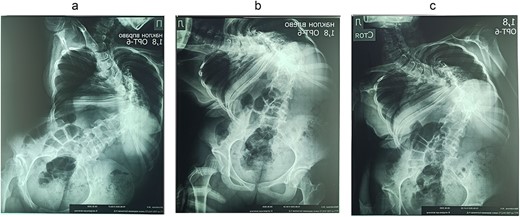

The rigidity of the scoliotic arch is noted on functional X-rays and on stretching (Fig. 3).

Preoperative functional X-ray: (a) inclination to the right, (b) inclination to the left, and (c) on stretching.